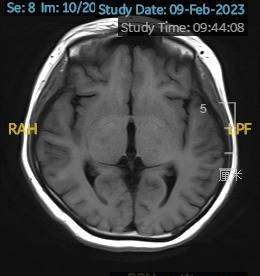

2023.03.27颅脑MR平扫示双侧基底节区及桥脑异常信号,考虑渗透性脱髓鞘综合征,较前范围略减小,请结合临床,见图4。

图4 2023.03.27双侧基底节区及桥脑见对称性片样长T1长T2信号,FLAIR呈高信号,较2023-02-24MR所示范围减小。脑室、脑池、脑沟、脑裂未见明显异常,中线结构居中。